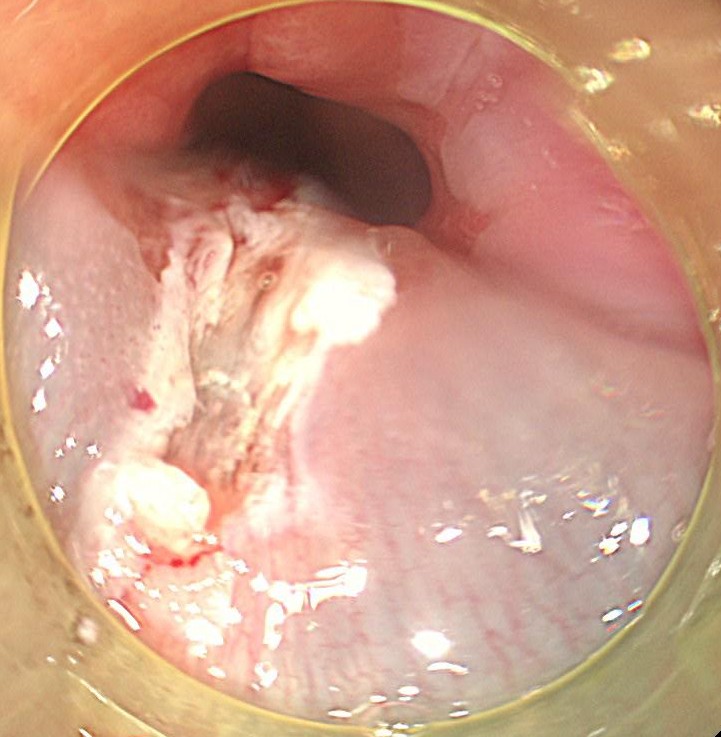

型のごとく、内視鏡切除 (EMR) しました。病理学的には悪性所見はありませんでしたが、高度な炎症細胞浸潤所見を認めました。典型的なバレット食道であり、今後も逆流性食道炎治療を継続しながら、注意深く経過をみていく必要があります。